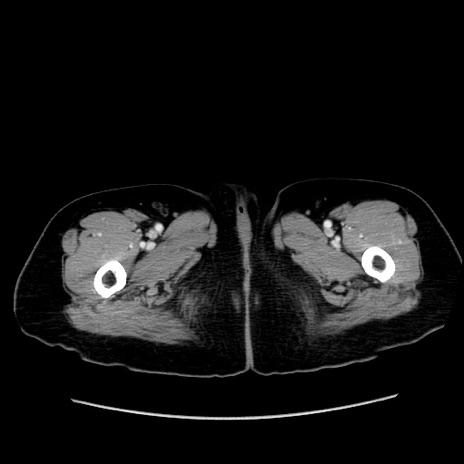

症例19(横断像)

【症例】80歳代女性

【主訴】下腹部痛

【現病歴】約8時間前より下腹部痛の出現あり、救急外来受診。

【既往歴】両側付属器切除

【身体所見】意識清明、下腹部正中に手術痕あり、その部位に一致して圧痛と反跳痛あり。腸蠕動音は亢進。

【データ】WBC 9300、CRP 0.15